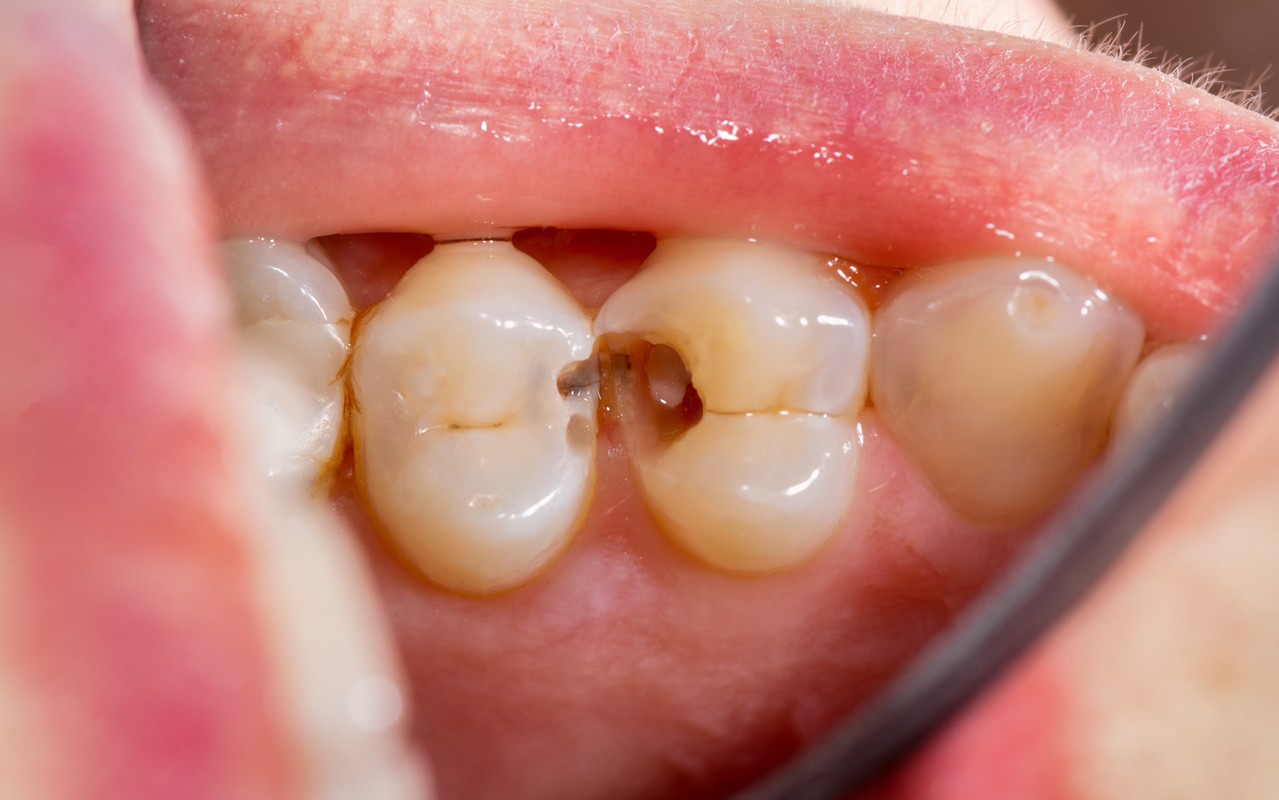

충치 단계별 치료방법

그 통증은 세균이 치아를 파고드는 신호일 수 있습니다.

충치의 깊이를 정확히 진단하는 것이 먼저입니다.

충치는 진행 단계에 따라 증상과 치료법이 완전히 달라집니다.

닥터조 치과는 현재 상태에 맞는 가장 좋은 방법을 정직하게 제시합니다.

STEP 02. 충치 2단계

증상 : 충치가 상아질까지 침범한 단계입니다.

차갑거나 단 음식이 닿을 때 찌릿한 통증을 느낄 수 있습니다.

치료 : 충치 범위에 따라 레진으로 간단히 때우거나,

내구성이 더 좋은 인레이/온레이로 치료가 필요할 수 있습니다.

STEP 03. 충치 3단계

증상 : 충치가 신경까지 침범한 단계입니다. 가만히 있어도

욱신거리고, 잠을 설치는 심한 통증이 있을 수 있습니다.

치료 : 충치에 감염된 신경을 제거해 통증을 없애고,

약해진 치아를 크라운으로 보호합니다.